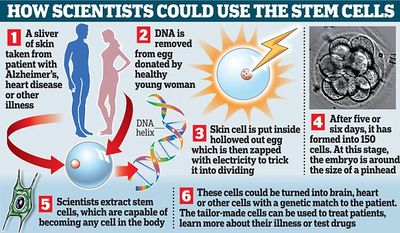

إختراق يمكن أن يؤدي إلى تخصيص الخلايا للمساعدة في علاج وحتى علاج مجموعة من الأمراض ، بداية من مرض الزهايمر حتى مرض التصلب المتعدد.

أولا، أخذ الدكتور ميتاليبوف Shoukhrat بويضات متبرع بها من قبل شابات بصحة جيدة وإزال الحمض النووي.

ثم وضع حينئذ خلايا الجلد داخل البويضات التى أزيل منها الحمض النووى واستخدم تيار ضئيل من الكهرباء لجعلها تبدأ النمو إلى جنين .

عندما كانت الأجنة قد بلغت خمسة أو ستة أيام من العمر، وكان حجما مثل رأس الدبوس، كان الدكتور ميتاليبوف جاهزا ليحصد منهم بنجاح الخلايا الجذعية.

هذه الخلايا، والمعروفة باسم "الخلايا الرئيسية"، قادرة على أن تتحول إلى كل نوع من الخلايا في الجسم، وينظر إليها على نطاق واسع أنها أطقم إصلاح محتمل لأجزاء الجسم المريضة، التالفة والمهترئة.

وباستخدام قطعة من جلد المريض مشربة بالفضة في بداية العملية ضمان أن الخلايا الجذعية ستكون نقلا مثاليا لأجسامهم.

وهذا من شأنه زيادة احتمالات الربح في هذه المعاملة أن تكون ناجحة، وإزالة الحاجة إلى الأدوية القوية لقمع النظام المناعي للمريض.

ويمكن أيضا أن الخلايا المصممة خصيصا استخدامها لمعرفة المزيد عن مرض الشخص، واختبار الأدوية للعثور على تلك التي تعمل بشكل أفضل.